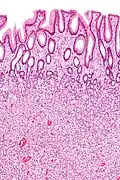

Hyperplastic polyp of the stomach Stomach Elongated, tortuous, and cystic foveolae separated by edematous and inflamed stroma.[14]

Gastric hyperplastic polyposis